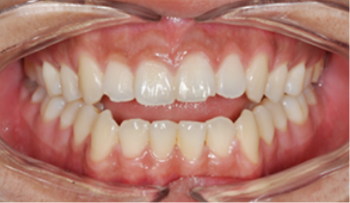

​​​​​​​Case 01. 덧니 & 치열 불규칙

덧니가 있거나 치열이 불규칙한 경우, 심미적으로도 보기에 좋지 않지만, 기능적으로도 본연의 역할을 상실하게 됩니다.

이 경우 교정 치료 방법은 크게 치아를 빼고 하는 방법과 치아를 빼지 않고 교정하는 방법으로 나뉩니다.

교정 치료 Before & After

• 덧니 & 치열 불규칙 교정 치료 전

Before

• 덧니 & 치열 불규칙 교정 치료 후

After